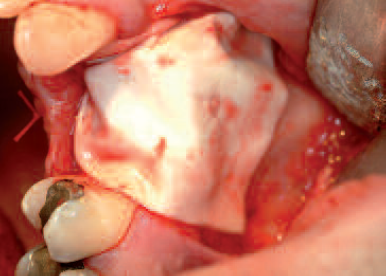

Inserted collagen membrane with perforation of the Schneiderian membrane in region 16 after insertion of implant

Collagen membrane cut to the defect size

Augmented material fully covered by the collagen membrane

Collagen membrane positioned above the defect before wound closure